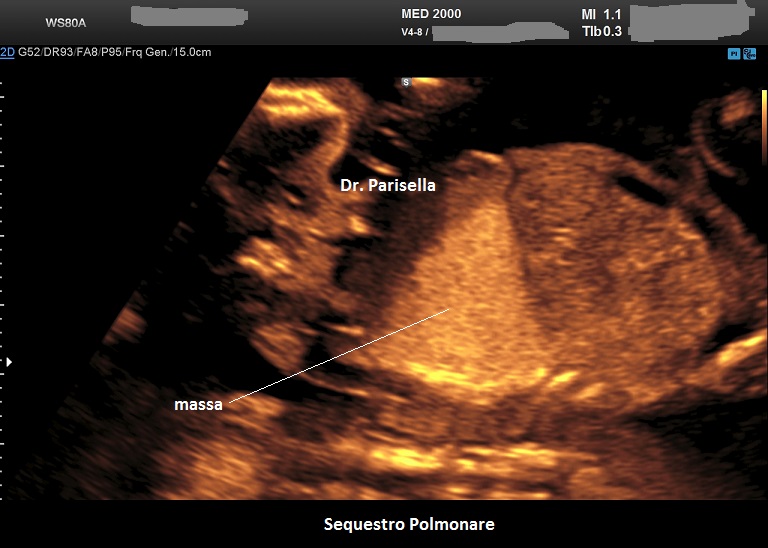

Sequestro Polmonare

Il Sequestro Polmonare è costituito da un'area di parenchima polmonare che non è in comunicazione con l'albero tracheo-bronchiale ed è tributaria della circolazione sistemica e non polmonare. E' una lesione monolaterale, localizzata nella maggior parte dei casi al lobo inferiore del polmone sinistro. Ne esistono due varianti:

• extra-lobare: è una forma più rara ed è quella classicamente diagnosticata in epoca prenatale; nel 90% dei casi è sopra-diaframmatica, nel 10% è sotto-diaframmatica. Caratteristicamente presenta un vaso afferente a partenza dall'aorta toracica o addominale.

Diagnosi ecografica

Si presenta come una lesione iperecogena localizzata più frequentemente al lobo inferiore del polmone sinistro, più raramente in sede sottodiaframmatica. Al Color-Doppler si evidenzia il vaso afferente a partenza dall'aorta toracica o addominale.

La diagnosi differenziale deve essere posta con la MACP: in questo caso è dirimente il riscontro di un vaso afferente originato dall'aorta nel sequestro polmonare a differenza della MACP in cui la massa è irrorata da diramazioni dell'arteria polmonare.